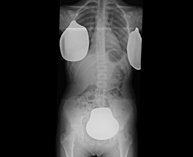

Estudi que usa els raigs X a través de la qual s'obtenen imatges del maluc i permet descartar luxacions. - RX Seriada òssia

Estudi que usa els raigs X a diferents parts del cos (crani, columna, costelles, pelvis, húmers i fèmurs) per descartar que existeixen lesions en aquests ossos. Indicacions: estudi del mieloma múltiple, gammapaties monoclonals, metàstasi. - RX Sacroilíaques